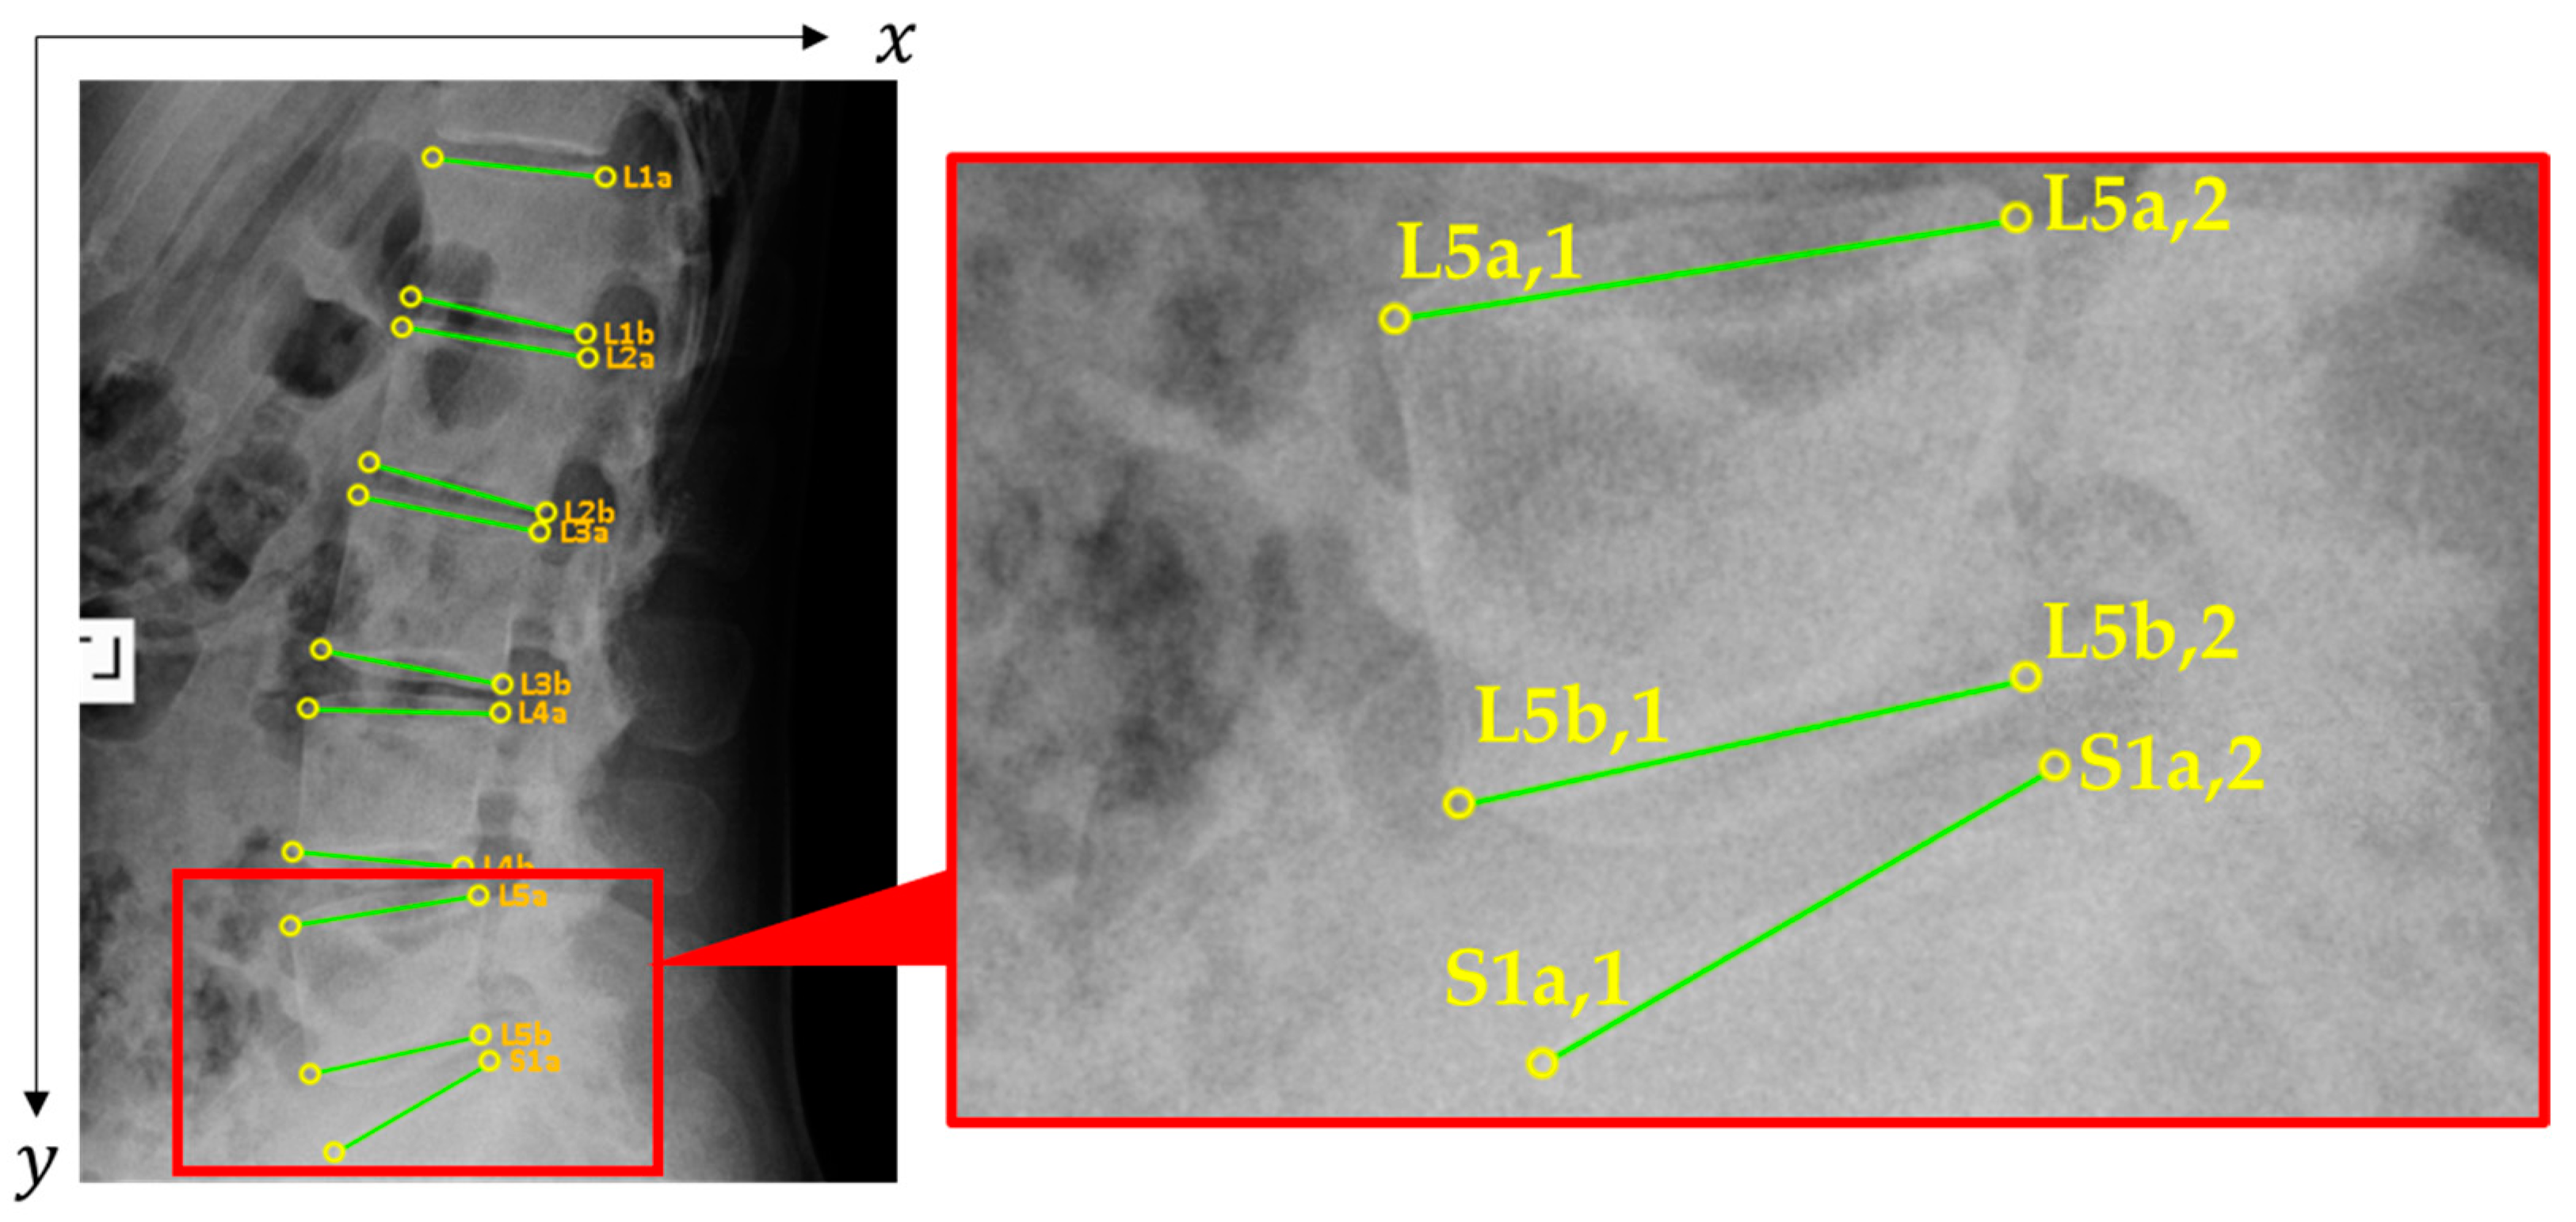

2.2.2. Spondylolisthesis

| Line | x1 | y1 | x2 | y2 | Class |

|---|---|---|---|---|---|

| L1a | 609 | 353 | 827 | 377 | ✕ 1 |

| L1b | 581 | 529 | 802 | 577 | 0 |

| L2a | 570 | 568 | 805 | 607 | ✕ 1 |

| L2b | 527 | 743 | 752 | 805 | 0 |

| L3a | 513 | 785 | 744 | 830 | ✕ 1 |

| L3b | 467 | 982 | 696 | 1025 | 0 |

| L4a | 450 | 1057 | 693 | 1063 | ✕ 1 |

| L4b | 430 | 1239 | 648 | 1259 | 0 |

| L5a | 427 | 1334 | 667 | 1295 | ✕ 1 |

| L5b | 452 | 1523 | 670 | 1474 | 0 |

| S1a | 483 | 1624 | 682 | 1508 | 0 2 |